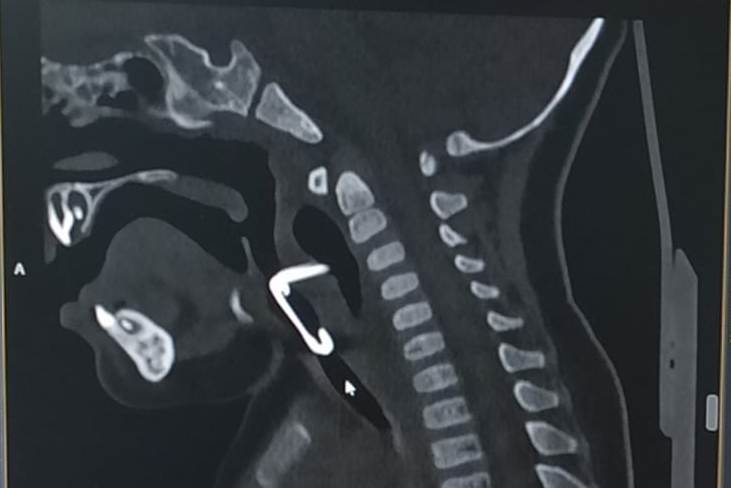

Проглотил болтик

Проглотил болтик 106 фотографий